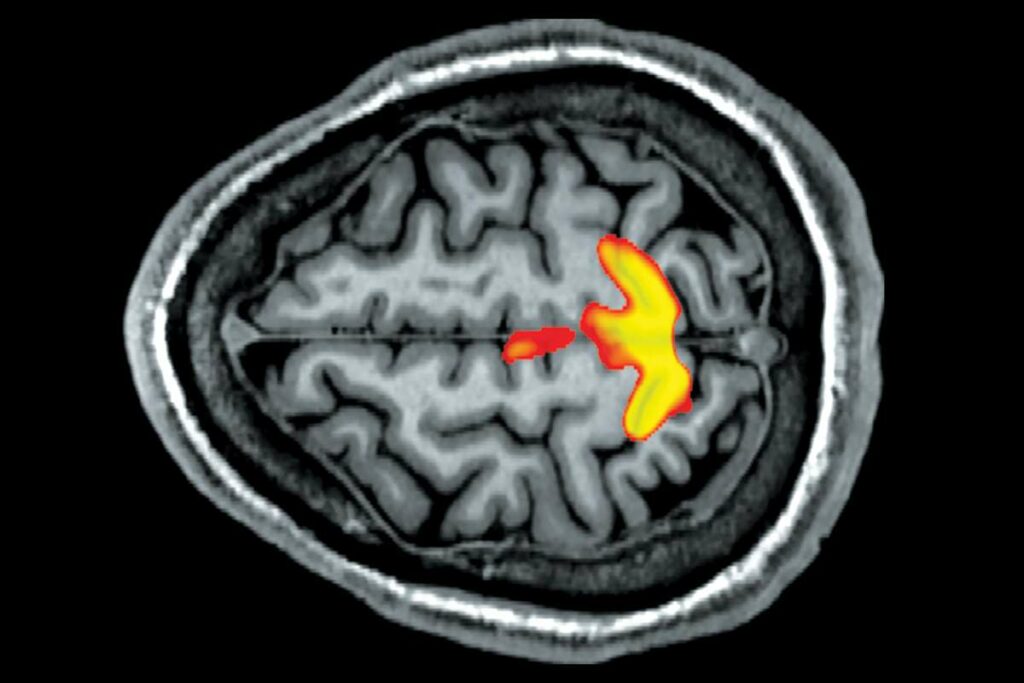

Μια ψυχοσωματική διαταραχή είναι μια ασθένεια, η οποία περιλαμβάνει τόσο το μυαλό, όσο και το σώμα. Μερικές σωματικές ασθένειες πιστεύεται ότι είναι ιδιαίτερα επιρρεπείς στο να επιδεινωθούν εξαιτίας παραγόντων ψυχικής υγείας, όπως το στρες και το άγχος.

Αυτά τα ψυχοσωματικά συμπτώματα οφείλονται στην αυξημένη δραστηριότητα των νευρικών ερεθισμάτων που στέλνονται από τον εγκέφαλο σε διάφορα μέρη του σώματος και στην απελευθέρωση της αδρεναλίνης (επινεφρίνη) στην κυκλοφορία του αίματος, όταν το άτομο είναι ανήσυχο και σε μεγάλο άγχος.

Ωστόσο, ο ακριβής τρόπος που το μυαλό μπορεί να προκαλέσει ορισμένα άλλα συμπτώματα δεν είναι σαφής. Επίσης, ούτε ο τρόπος που ο νους μπορεί να επηρεάσει τις καθεαυτές σωματικές παθήσεις (εξανθήματα, αρτηριακή πίεση, κλπ) είναι σαφής. Μπορεί να έχει να κάνει με τα νευρικά σήματα που διαχέονται στο σώμα και τα οποία δεν καταλαβαίνουμε πλήρως. Υπάρχουν, επίσης, κάποια στοιχεία ότι ο εγκέφαλος μπορεί να είναι σε θέση να επηρεάσει ορισμένα κύτταρα του ανοσοποιητικού συστήματος, το οποίο εμπλέκεται σε διάφορες σωματικές ασθένειες.